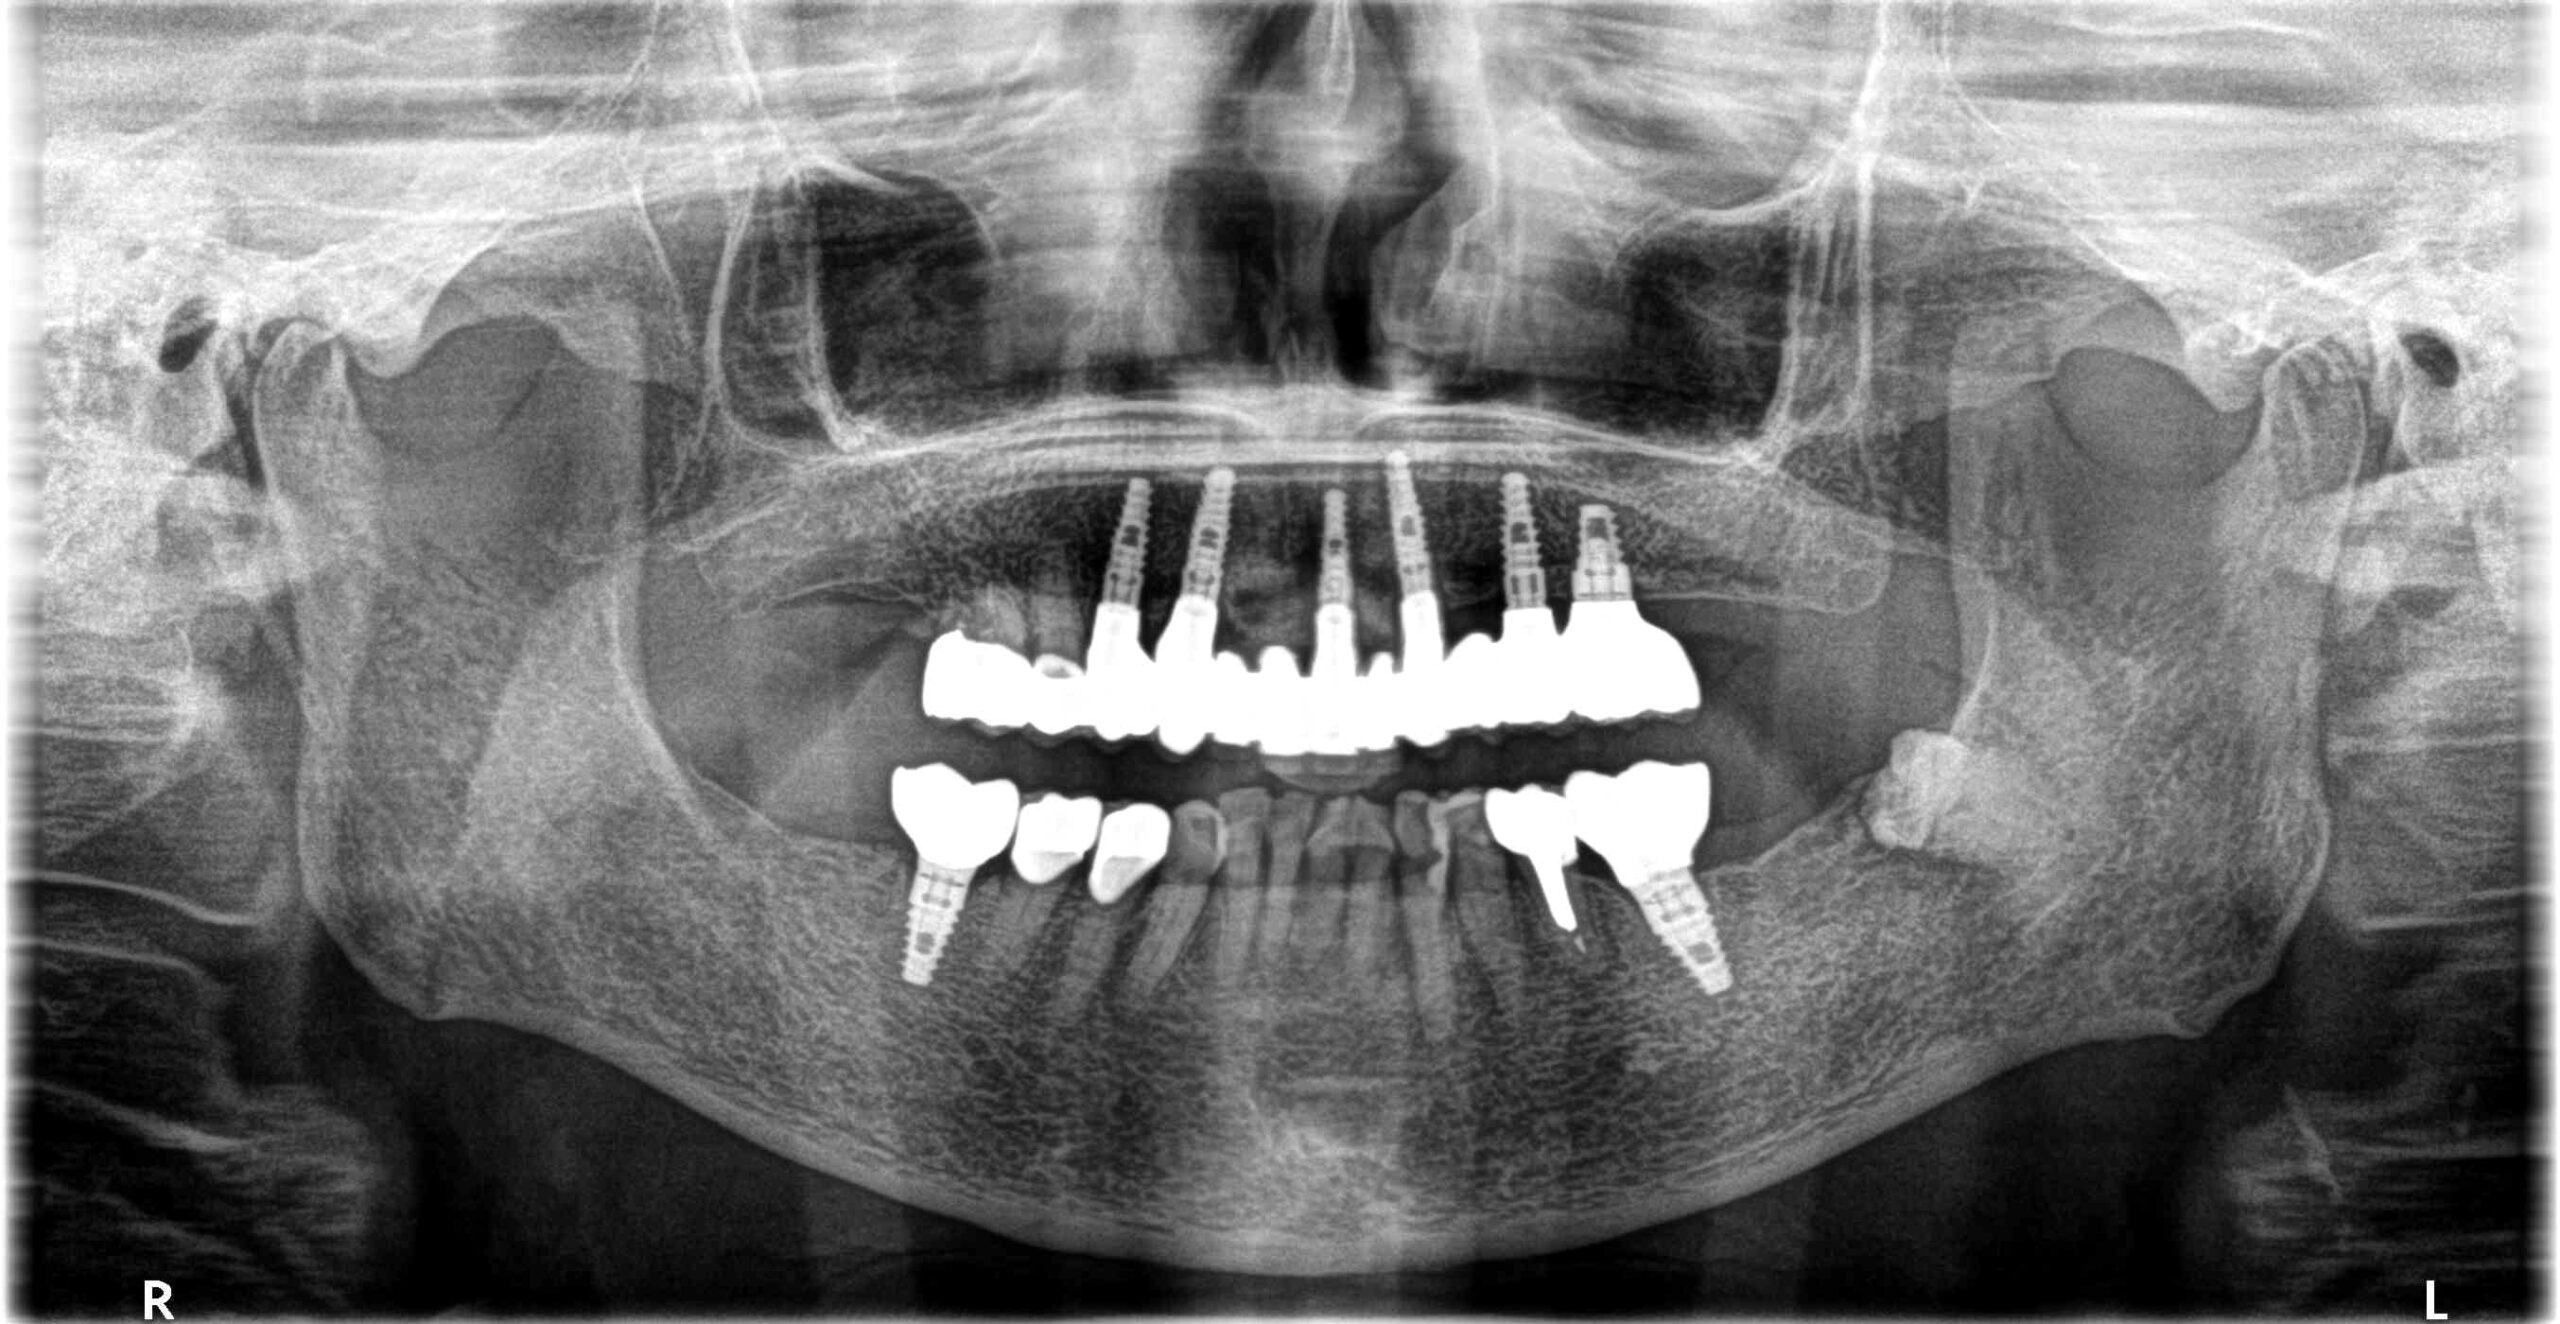

治療経過 高齢ではあったが、入れ歯はどうしてもいれたくないということでインプラントを選択。

上顎は長期的な予後が見込める歯が少なく多数のインプラントを必要としたが、一時的にも義歯を使うことなく、咬める場所を温存しながらインプラントへと移行できた。

初診時不安定だった咬み合わせもスムーズに行えるようになり、不安なく食事ができるお口の状態を獲得できた。